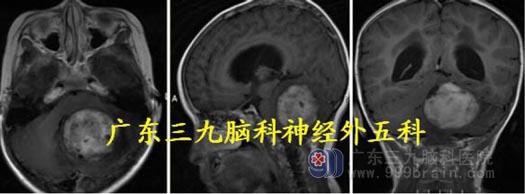

头颅MR:小脑蚓部、四脑室区示类囊状长T1 长T2 病灶,同时可见多发流空信号影,

并可见一粗大引流血管,病灶范围约40.8mm×40.8mm×52.7mm,增强后环壁不均匀强

化,边缘不光整。考虑血管母细胞瘤及幕上梗阻性脑积水。

MR 灌注测值395.61±232.75ml/100g/min;提示病灶高灌注,血供极其丰富。